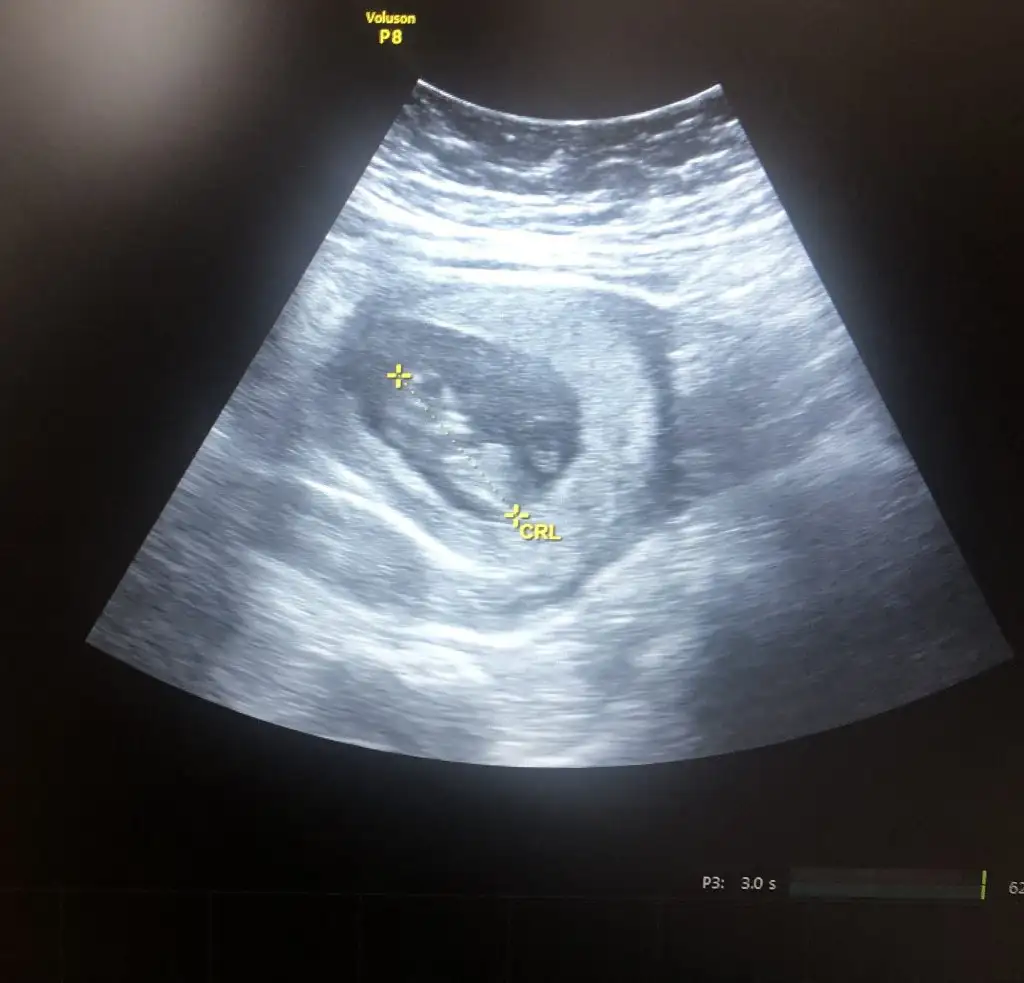

T Tali89 merhaba benim yavrumada bı el atar mısın 🤭10+1 karından

• IMG_20240222_194903.webp

IMG_20240222_194903.webp

17,3 KB · Görüntüleme: 60